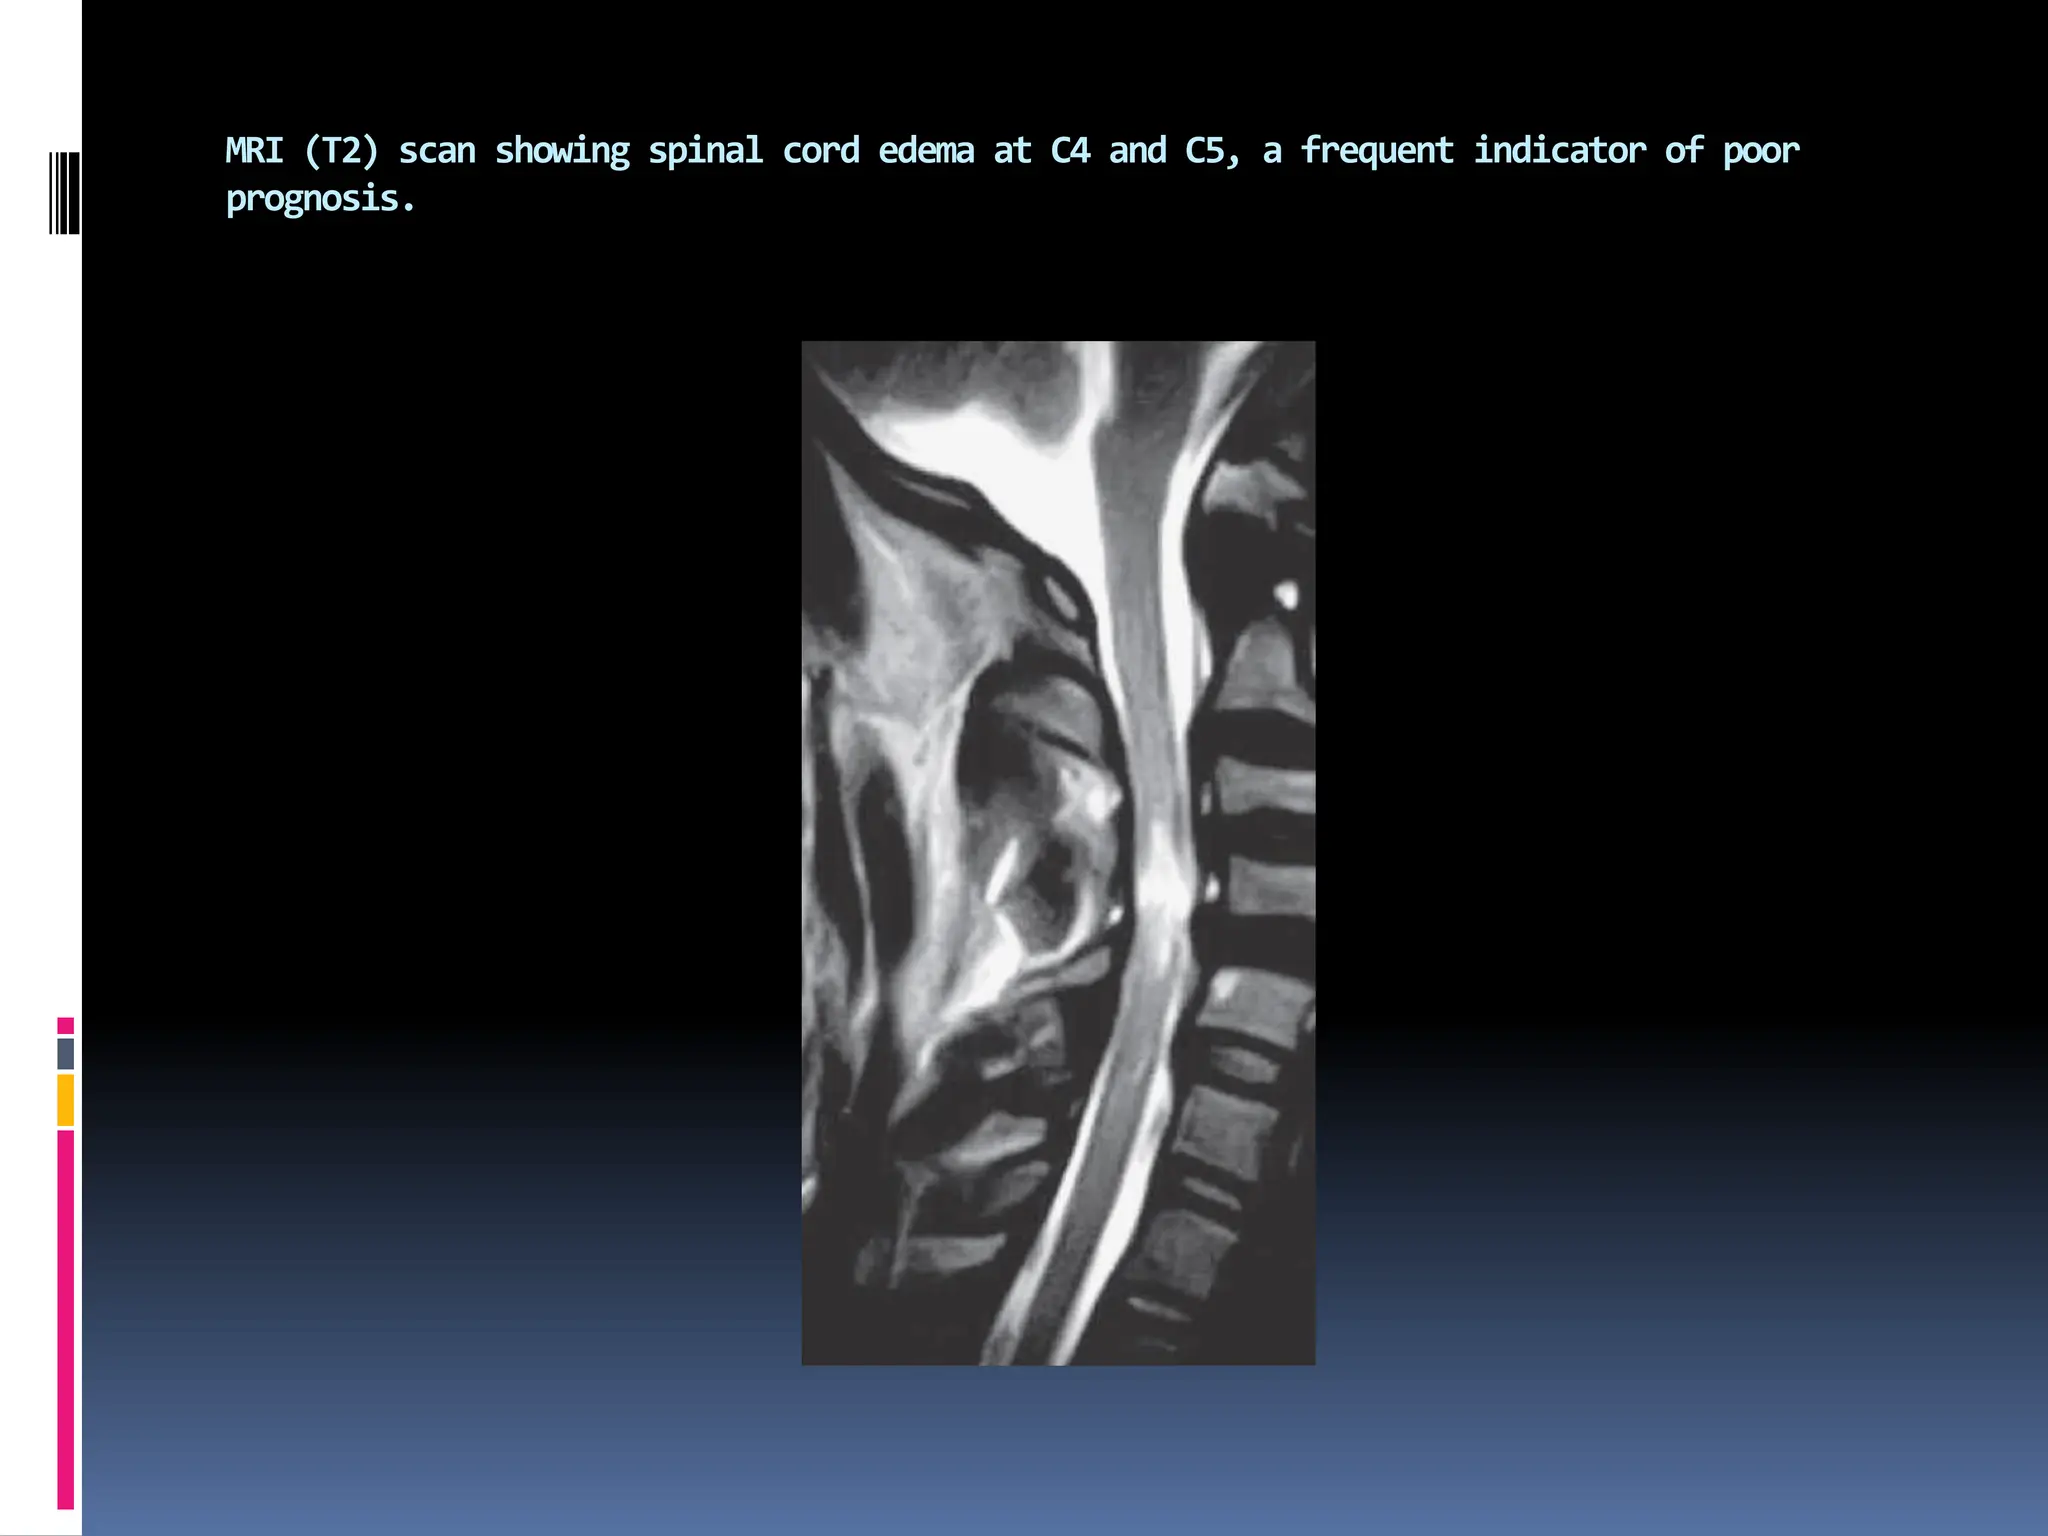

▪ C4–C5 edema is a frequent indicator for a poor prognosis.

MRI (T2) scan showing spinal cord edema at C4 and C5, a frequent indicator of poor

prognosis.